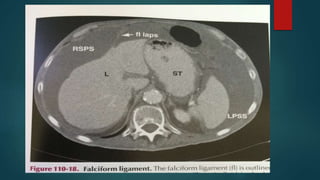

Falciform ligament Connects liverto the posterior aspect of the anterior abdominal wall just right to the midline

Right sided supramesocolic spaces The right sub diaphragmatic space is limited anteriorly by the falciform ligament and posteriorly by the upper layer coronary ligament

Falciform ligament

Connects liver to the posterior

aspect of the anterior abdominal

wall just right to the midline